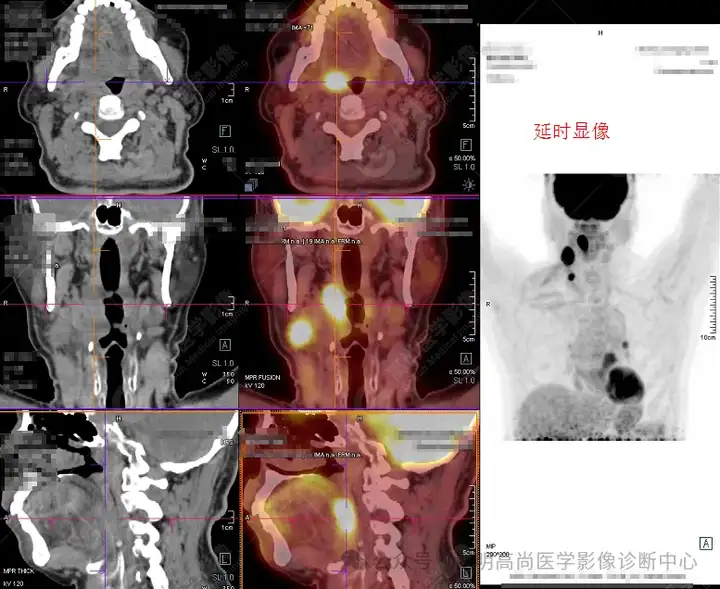

口咽右侧壁及右侧颈部多发高代谢灶

延时显像口咽右侧壁及右侧颈部病变糖代谢持续增高

右颈部多发高代谢淋巴结1

1、口咽部右侧壁及部分前壁增厚并右侧腭扁桃体区肿块影形成,糖代谢持续明显增高,考虑恶性病变,建议对口咽右侧壁活检;

2、 双颈颈Ⅱ、Ⅲ、Ⅳ、Ⅴ区、左肺门(10组)及纵隔(4、5组)多发淋巴结显示,其中右颈Ⅱ、Ⅳ区、左肺门(10组)及纵隔5组淋巴结明显增大并糖代谢持续不同程度增高,符合转移淋巴结表现,余淋巴结反应性增生可能,建议随诊。